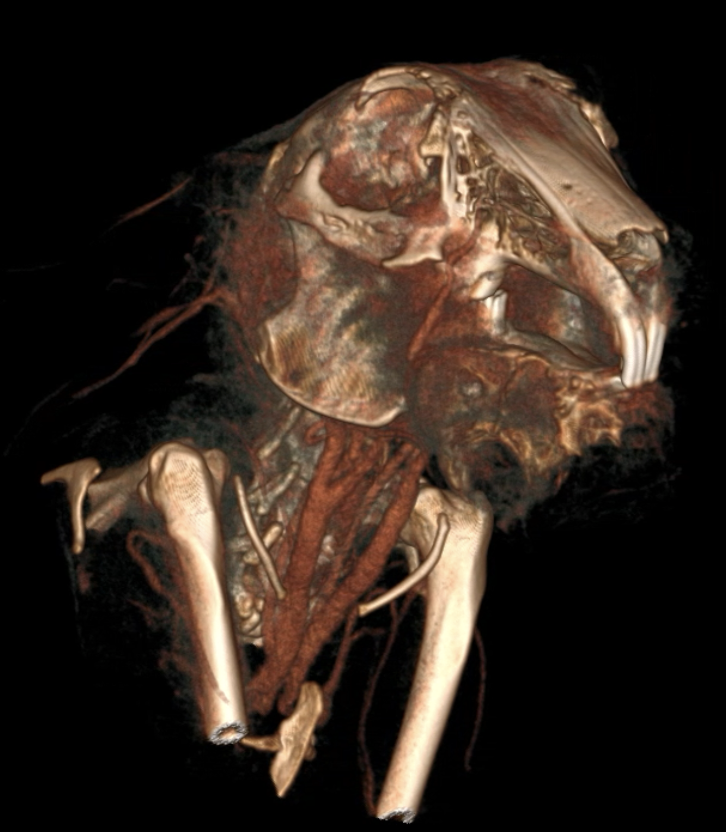

3. Heutzutage haben wir Zugang zu den neusten Technologien. Mit den neuen CBCT-Geräten, Flatpanel Röntgenplatten und dentalen Röntgen können wir gestochen scharfe Bilder von Kaninchen bis zu Degu-Schädeln machen. Diese Technologie hat es aber auch verdient, dass man sie richtig benutzt. D.h. die Tiere sollte perfekt gelagert werden und am besten in Sedation oder Narkose, damit man auch sehr gute Bilder bekommt.

Grundsätzlich profitieren alle Kaninchen, Meerschweinchen und Chinchillas mit Zahnerkrankungen von CT-Aufnahmen, da die Aufnahmen schnell erstellt sind und viel mehr Informationen liefern als Röntgenbilder. Vor allem bei Tieren mit Abszessbildung empfiehlt sich eine CT-Untersuchung, um Operationen, bzw. Extraktionen besser planen zu können. Idealerweise sollten diese dann auch mit Kontrastmittel durchgeführt werden. Aber auch Otitis und Rhinitis sind zwei Erkrankungen bei Kaninchen, welche idealerweise durch CT-Untersuchungen weiter abgeklärt werden.